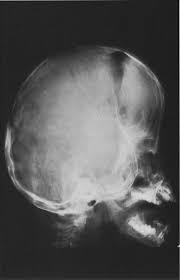

Copper beaten skull

A

Primary:

Raised intracranial pressure in children.

Other:

Craniosynostosis

Obstructive hydrocephalus

Hypophosphatasia

Intracranial masses